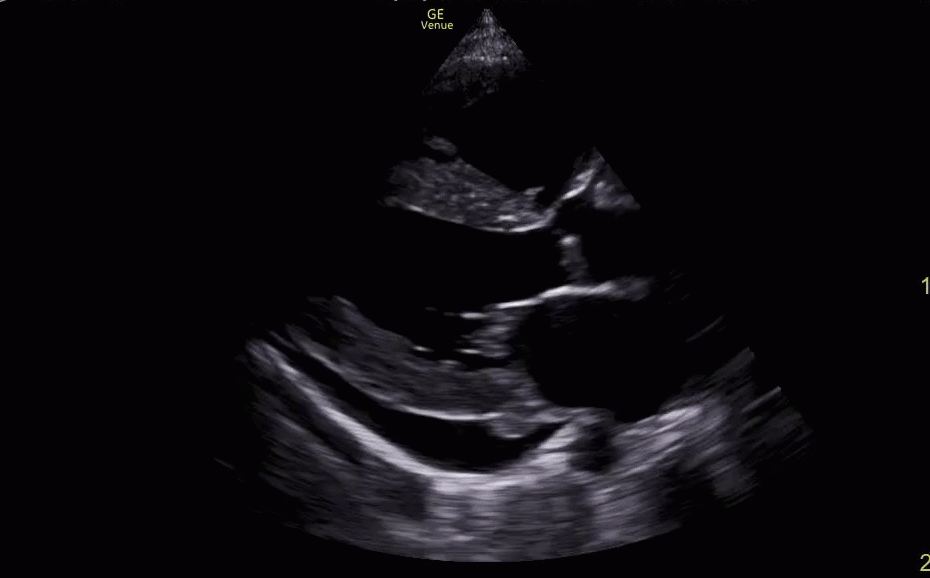

Pericardial and Pleural Effusions

Pericardial Effusion

Pacer Lead Migration

Mitral Valve Prolapse

Left Atrial Mass

Complete Heart Block

Atrial Flutter

Supine vs Left Lateral Decubitus

Normal 4 View Echo